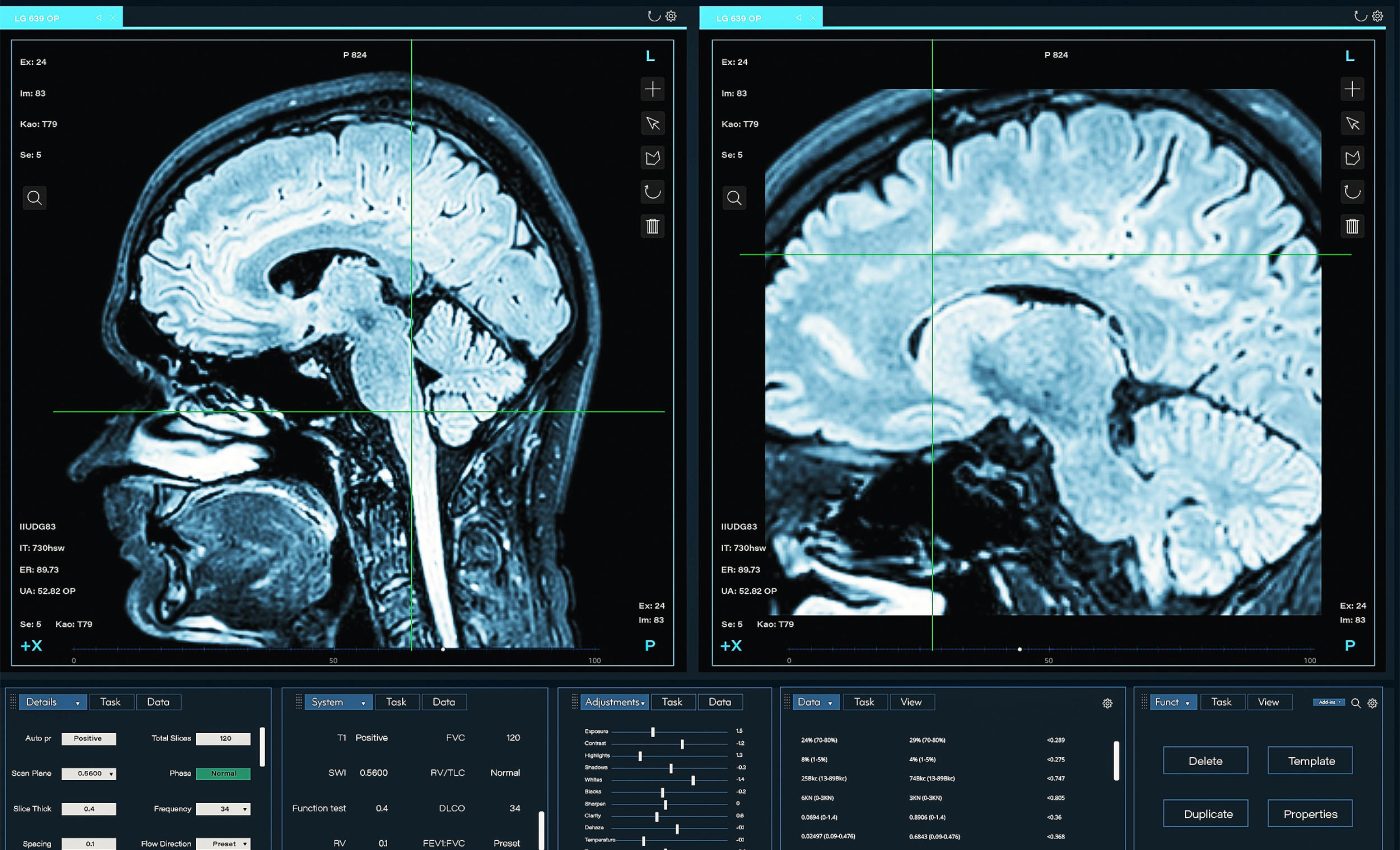

The study pooled 139 neuroimaging reports with 3,765 participants aged 5 to 85, charting how conflict-related brain activity shifts with age. It used a standardized approach to combine many small studies into a single, age-by-activity curve.

Researchers relied on seed-based d mapping to summarize whole-brain activation patterns.

They then fit age curves with a generalized additive model and compared them to simpler functions to see which shape best explained the data.